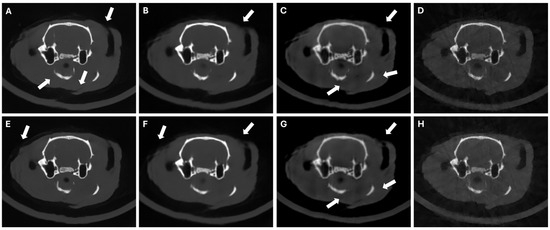

3.4. Results in Highly Limited-Data Scenarios